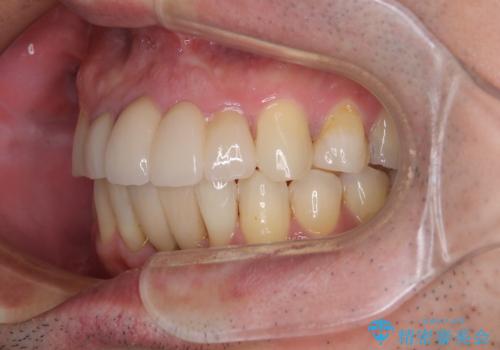

上顎前歯もインプラントを希望していらっしゃいましたが、両隣の歯根が近接しており、インプラントは困難と判断したためオールセラミックブリッジによる補綴治療を前提として治療を開始することとしました。

在宅勤務のため、前歯にスペースが長期間できることに対して特に問題はないとおっしゃったため、スペースはそのままに治療を進めていくこととしました。

下顎前歯にインプラントを2本埋入するのは非常に困難であり、どうしても歯肉位置に土台の金属色が見えてしまう仕上がりとなりました。無理をせずに1本のみの埋入とするか、ブリッジを提案しましたが、患者様の強い希望により、2本埋入することとなり、大変満足していただけました。